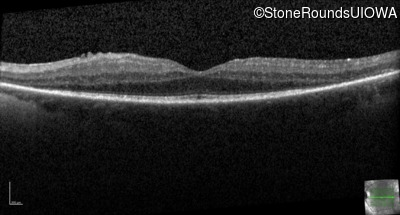

Optical Coherence Tomography - Right - 20/25 -1

Exemplar / OCT Stack

OCT Stack